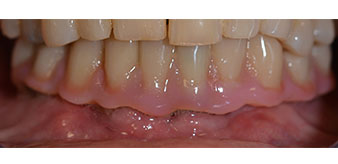

dentición residual

Fig. 2

El tratamiento periodóntico necesario y la extracción de las piezas en el maxilar superior debía realizarse en un momento posterior, ya que la paciente es profesora y, en el momento de la consulta, estaba ocupada con los exámenes para las pruebas de acceso a la universidad. La paciente no podía comer ni hablar adecuadamente, ya que la prótesis temporal se rompía con mucha frecuencia y con una carga mínima.

Tras explicarle las distintas opciones de tratamiento, la paciente se decidió por la extracción de la dentición residual en el maxilar inferior, la implantación inmediata y el tratamiento con el método Fast & Fixed (bredent medical), con el que la prótesis dental fijada provisionalmente se atornilla sobre cuatro implantes en el mismo día de la intervención. El objetivo era operar a la paciente el viernes para que el lunes pudiera tomar parte en los exámenes orales para la prueba de acceso a la universidad.